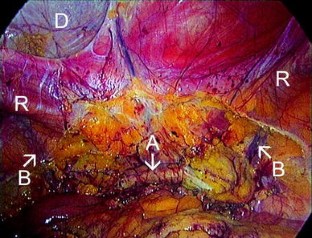

Fig. 3